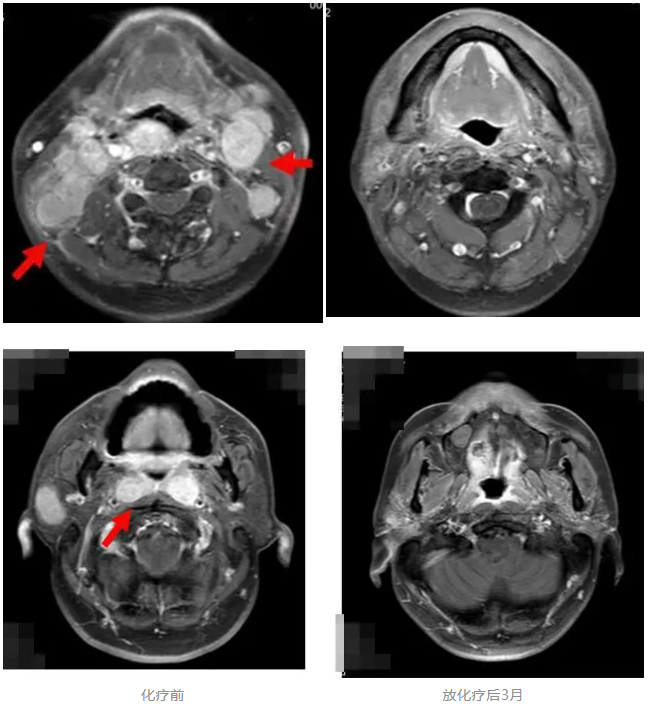

2017年4月,患者林先生(化名)确诊非角化性未分化型鼻咽癌伴双颈部及锁骨上淋巴结转移、肝转移,血EB病毒DNA载量(EB-DNA)高达176000拷贝数/ml,病情已达晚期。经TP方案全身化疗及容积旋转调强放疗(VAMT)后,EB-DNA成功清零,影像复查肿瘤基本消失。患者个人原因未行进一步维持治疗,后门诊定期复查。